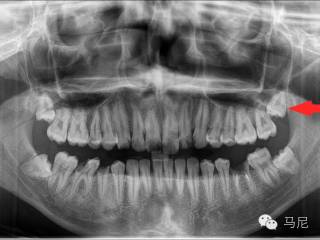

拔牙前的风险和难度预判非常重要。术者需要在拔牙前应针对病人主诉问题进行详细口内检查、仔细确认所需拔除的牙齿,了解患牙情况及其与邻牙、周围组织的关系。所有患者常规均应行术前X线片检查,对于根尖片无法满足手术需要的病例,则需进一步拍摄牙科CT,了解牙齿形态、结构及与周围重要解剖结构(如上颌窦、下颌神经管等)的位置关系。术前与患者及家属进行良好的交流和沟通,交代拔牙术过程及术中、术后的相关事项,以缓解患者的紧张、恐惧心理,取得其信任与配合。对于高度紧张或牙科恐惧症患者,术前应采用镇痛、镇静等措施,以达到心理、精神的微创。此外,根据术前预判和设计,准备合适的微创拔牙器械。

4, 分牙

通过将患牙牙体组织恰当分割,化整为零,从而解除患牙拔除时的各方阻力,使操作尽量在患牙内进行,是微创拔牙术的精髓,也是最能体现医生技术水平的关键环节。分牙的目的是为了减小患牙冠和(或)根部骨阻力或解除邻牙的阻力分牙,可包括截冠、分根以及在患牙牙体组织内任意分块切割,适用于各种复杂牙、埋伏牙,尤其是患牙有两根及两根以上,根分叉较大而难以拔除的牙齿。通过分切牙齿,使多根牙转化为单根牙,大牙变小牙而轻松解除阻力,术中准确的分牙设计和操作是将牙齿又快又好地拔除的关键。不同类型的牙齿,分牙方法也是不同的,总体来说以分割块数和次数越少越好,以最小和最少的分割方式进行,有利于减少操作时间、减少创伤和降低并发症。推荐使用马尼加长版1557。加长版1557是外科用长柄车针,全长有25mm和28mm,刃部设计采取十字切割,高效安全,不易折断。